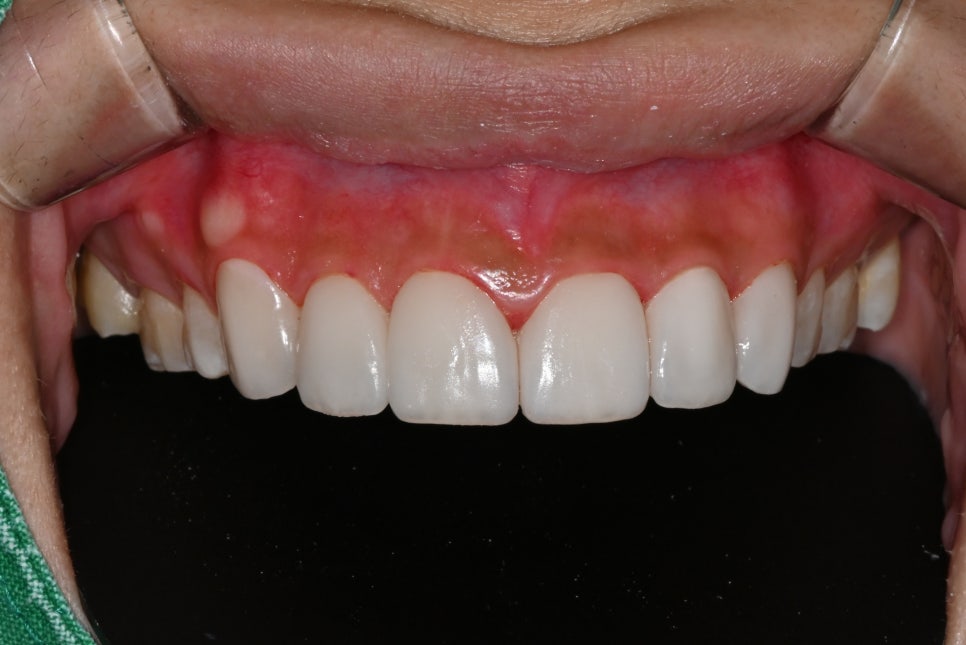

📸 After

– 밝고 매끄러운 치아 톤

– 균형 잡힌 앞니 라인

– 미소선과 조화되는 자연스러운 조형

환자분은 “치아가 예뻐졌다기보단, 내 얼굴이 환해진 느낌”이라며

처음으로 사진 찍을 때 입을 활짝 열어 웃게 됐다고 전해주셨습니다.